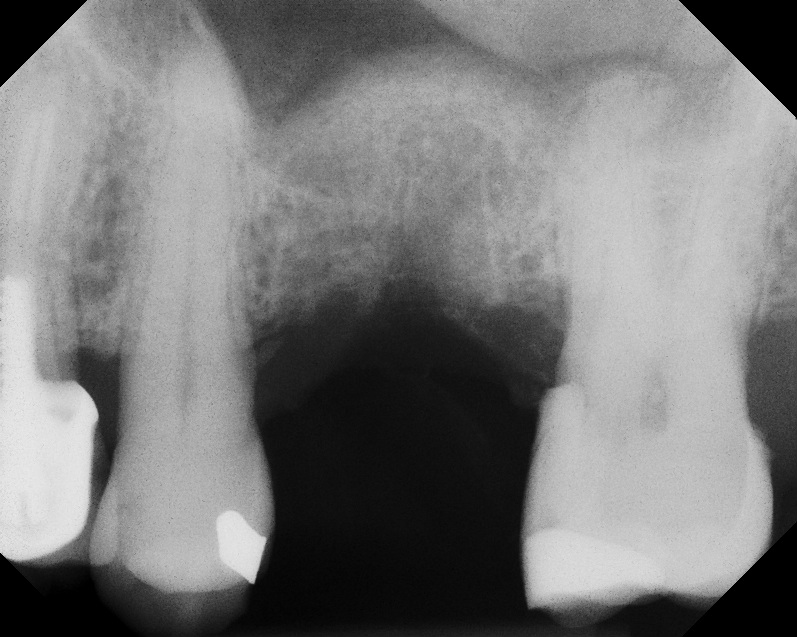

Case 1. Preoperative radiograph showing a ridge height of about 2 mm to 3 mm in the No. 14 position.

Fig. 13